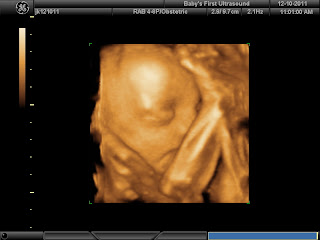

Our little blessing in 3D

Today hubs & I had a date that we will never forget.

For a half hour, we sat in amazement watching our little girl making all kinds of faces at us.

Sienna - you are one adorable little girl, We cannot wait to meet you on your birthday...maybe on your mom & dads birthday - it would certainly be the best birthday present under the sun.

my little smiley girl